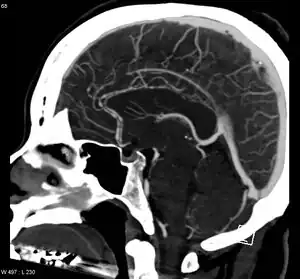

Significant beading of all intracranial arteries, best demonstrated in the anterior cerebral arties due to RCVS.

RCVS is diagnosed by detecting diffuse reversible cerebral vasoconstriction.[2] Catheter angiography is ideal, but computed tomography angiography and magnetic resonance angiography can identify about 70% of cases.[2] Multiple angiographies may be necessary.[2] Because other diseases (such as atherosclerosis) have similar angiographic presentations, it can only be conclusively diagnosed if vasoconstriction resolves within 12 weeks.[2]